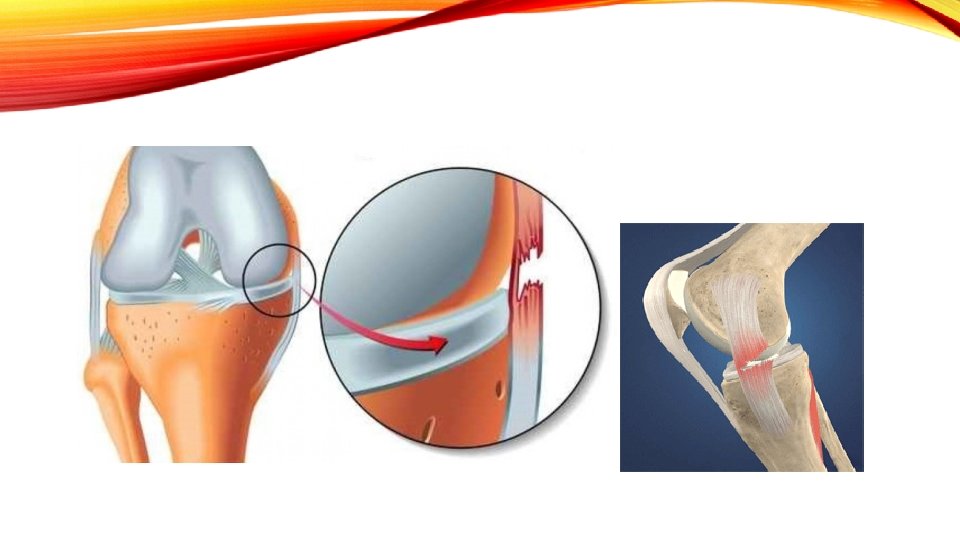

MENISCUS • Mechanism: Acute cutting; rotational force; or degeneration - overuse • Signs/Symptoms: Tenderness, swelling in joint line; swelling in popliteal fossa for posterior tear; knee feels as if it gets “locked”; lacks full extension/flexion; pain with squatting, positive stress tests • Special Tests: Mc. Murray’s; Apley’s Compression/Distraction and Duck Walk • Medial Meniscus is torn more often than lateral – prone to valgus stress and not very mobile; attached to deep part of MCL;

CAN MENISCAL TEARS BE REPAIRED? • Outside edge of each meniscus: red/red zone – repairable • Inner portion is the avascular edge; unrepairable; white/white zone • Outside to inside: red/white zone – usually not repairable • Age consideration, location of tear – factors on whether to repair or remove. • Removal will be as little as possible to maintain function